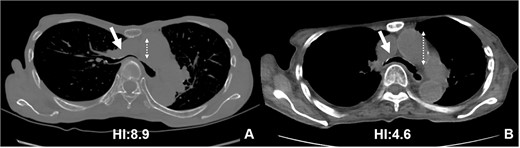

Based on these imaging tests, surgery for oropharyngeal cancer caused breathing difficulties due to a leftward shift of the trachea. The sternum’s depression led to severe narrowing of the right main bronchus, and age-related factors added to the respiratory distress. We performed a Nuss procedure for PE repair to release the stenosis of the right main bronchus surgically. As thoracoscopy revealed a depressed sternum, we corrected the sternal depression by sternal elevation using two pectus bars. Postoperative chest CT showed improvement in the sternal depression (HI:4.6, Fig. 3B) and right main bronchial stenosis (Fig. 4B). Furthermore, shortness of breath was relieved postoperatively.

Pre- (A) and postoperative (B) CT findings: the Nuss procedure improved the chest wall and right main bronchus stenosis, and reduced HI from 8.9 to 4.6.